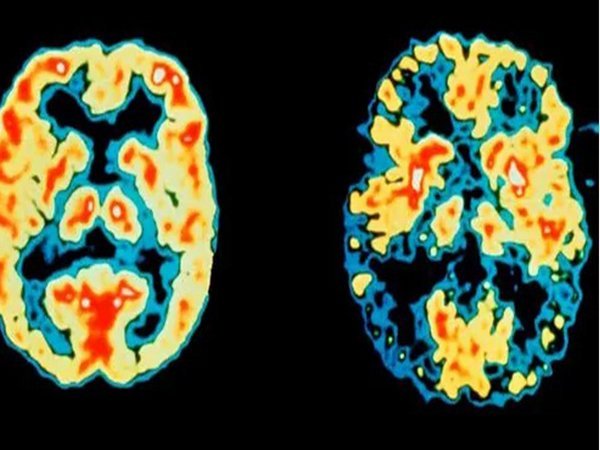

تشخیص آلزایمر۷ سال قبل از بروز اولین علائم

تهران-ایرنا- محققان انگلیسی آزمایش ساده ای برای حافظه ابداع کرده اند که به وسیله آن می توان آلزایمر را هفت سال قبل از بروز اولین علائم این بیماری تشخیص داد.به گزارش گروه علمی ایرنا از روزنامه تلگراف، تا اکنون تمام آزمایش های دارویی برای معکوس کردن بیماری آلزایمر با شکست روبرو شده اند و بیشتر محققان معتقدد که این بیماری را تنها از طریق تشخیص زودهنگام و قبل از بروز آسیب های غیرقابل جبران آن، می توان کنترل کرد. محققان دانشگاه کالج لندن در آزمایش جدیدی که در مجله The Lancet Neurology منتشر شده است، نشان دادند که یک آزمایش ساده حافظه می تواند اولین علائم مربوط به زوال عقل را حتی در زمانی که هنوز سایر علائم ظاهر نشده اند، تشخیص دهد.محققان معتقدند که این آزمایش، زودهنگام ترین روش برای تشخیص تغییرات در وضعیت شناختی افراد است که به بیماری آلزایمر منجر می شوند.این آزمایش در واقع نحوه خوب عملکردن حافظه را بعد از یک هفته بررسی می کند. محققان در این مطالعه یک گروه ۳۵ نفره را مورد بررسی قرار دادند؛ ۲۱ تن از این افراد حامل جهشی بودند که آنها را در معرض خطر بالاتر ابتلا به آلزایمر در دهه ۴۰ و ۵۰ سالگی قرار می دهد. محققان از این افراد خواستند که فهرستی از اشیاء، جزئیات یک نمودار و واقعیت های یک داستان را به یاد آورند. در آزمایش هایی که در حال حاضر برای بررسی حافظه وجود دارند، از افراد خواسته می شود که جزئیات را بعد از ۳۰ دقیقه بیادآورند. اما در این آزمایش جدید، این زمان تا هفت روز به تاخیر افتاده است. محققان در این مطالعه جدید متوجه شدند که افراد حامل جهش و افرادی که انتظار می رود در عرض هفت سال به آلزایمر مبتلا شوند، توانستند این موضوعات را در ۳۰ دقیقه بیادآورند، اما عملکرد حافظه آنها در هفت روز به اندازه قابل توجهی کاهش یافت.پروفسور ‘نیک فاکس’ مدیر مرکز تحقیقات زوال عقل و استاد نورولوژی در دانشگاه کالج لندن، گفت: آزمایش های فعلی در خصوص بسیاری از افراد که احساس می کنند مشکلی در حافظه آنها در حال رخ دادن است، چیزی نشان نمی دهند زیرا ۳۰ دقیقه واقعا مدت زمان کافی نیست.وی افزود: اما این مطالعه جدید نشان داد که افراد حامل جهش و افرادی که در مرحله ابتدایی ابتلا به آلزایمر قرار داشتند مشکلی در رابطه با یادآوری مطالب بعد از ۳۰ دقیقه نداشتند اما در هفت روز حافظه آنها بسیار بد شد بطوریکه این تفاوت کاملا قابل توجه است.محققان با وجود اینکه این مطالعه تنها بر افراد حامل جهش ژنتیکی APP انجام شد ، معتقدند که این آزمایش برای بیماری آلزایمر اسپورادیک (نوع بسیار شایع آلزایمر که تقریبا ۹۰ تا ۹۵ درصد از موارد ابتلا به آلزایمر را شامل می شود) نیز کارایی دارد و می تواند در آینده به تشخیص این بیماری کمک کند.